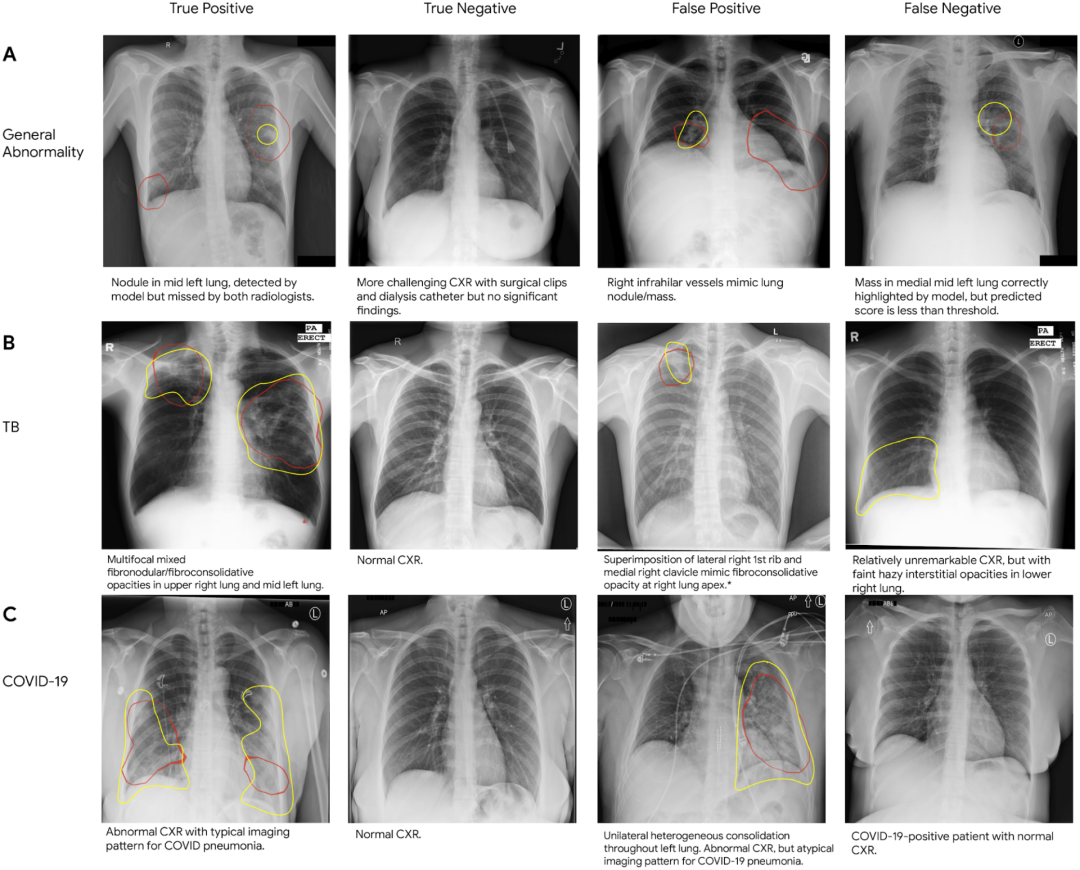

A:一般异常情况、B:结核病、C:COVID-19的真阳性,真阴性,假阳性,假阴性的胸部X光片样本

在每张CXR上,红色的轮廓表示模型集中识别异常的区域,黄色的轮廓指的是由放射科医生识别的区域。